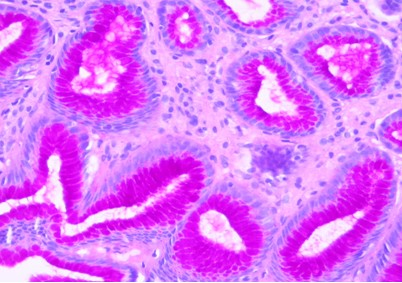

2.3 GS组织样本制备套液制作的石蜡切片,肾组织进行PAMS染色,胃粘膜组织行PAS组织化学染色,结果显示,肾小球基底膜和胃组织中的中性粘液染色清晰,色泽鲜艳,阳性物质定位准确,与传统方法制片染色效果相同(图4,5)。

图5 胃黏膜组织:中性黏液呈红色。PAS×400